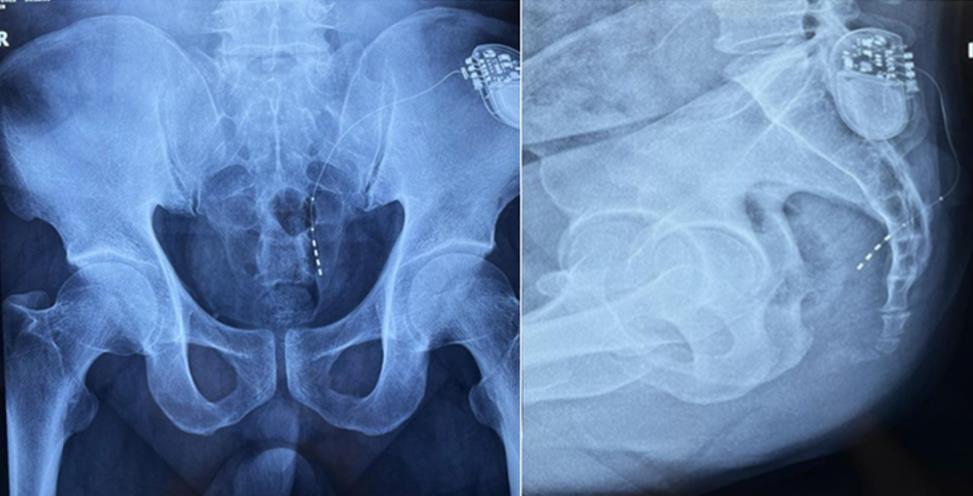

該患者兩年前被診斷患有膀胱過度活動癥(OAB),出現(xiàn)嚴(yán)重尿頻、尿急、尿細(xì)線等癥狀,醫(yī)生為其做了骶神經(jīng)調(diào)控手術(shù)。近期,患者癥狀又開始加重,生活質(zhì)量受到影響,為減輕癥狀,改善生活,患者前往南醫(yī)大二附院就診。衛(wèi)中慶主任及其團隊在查看患者病情后,決定重新調(diào)整電極刺激位置,將刺激點由原左側(cè)骶4神經(jīng)孔改為骶3神經(jīng)孔,通過新的神經(jīng)調(diào)節(jié)順利地改善了癥狀。

患者術(shù)前影像